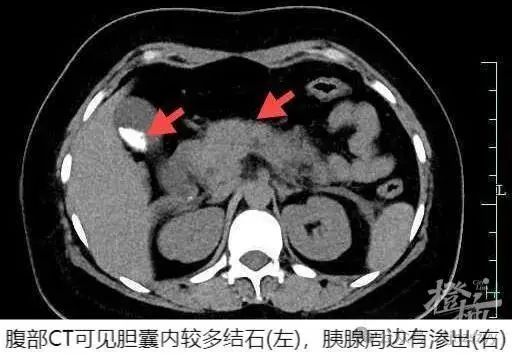

根据检查发现血清淀粉酶明显升高以及CT影像上胰腺水肿的结果,明确诊断为急性胰腺炎,需马上安排住院。

黄海表示小慧得的胆源性胰腺炎是中国急性胰腺炎的主要类型,其中胆道结石是最常见的原因。这种类型的胰腺炎通常起病急、变化快,合并多脏器功能衰竭的重症患者病死率高达20%~30%。小慧虽然提前发现了胆囊结石却没有引起足够的重视,没有管住嘴。